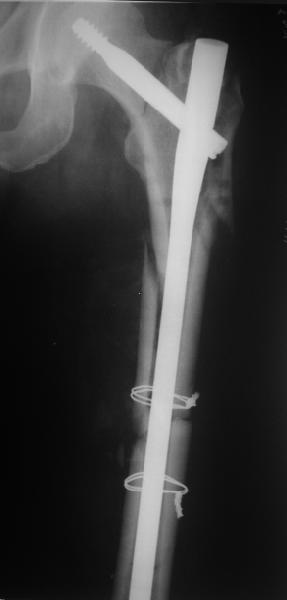

В общем, сделали. См. приложение.

Длина и из-за этого ось получились не совсем такие, как хотелось бы, все-таки срок после той операции уже 6 недель. Может быть, стоило провести дистракцию аппаратом неделю-другую. Заранее спасибо за комментарии и критику.

Здесь сканнированные снимки импланта и операционные снимки больной.

Итог